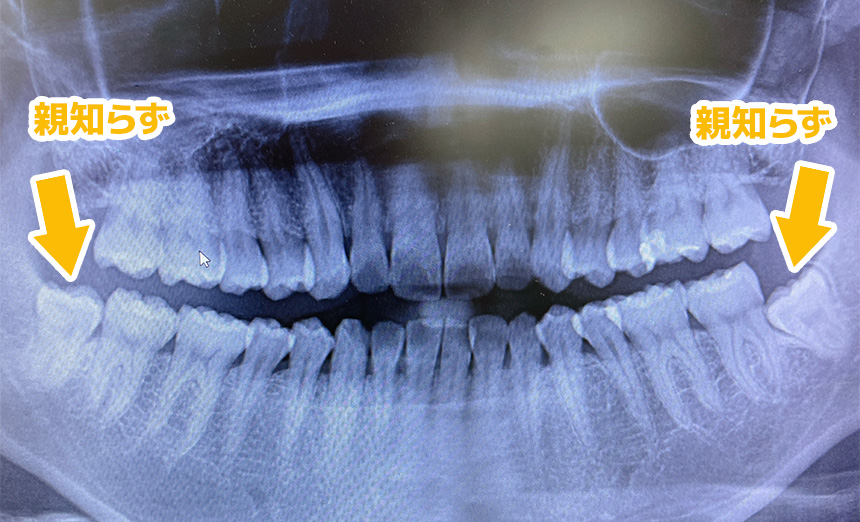

簡単に言うと、自分の親知らずを⻭を抜いたところに移植する治療法となります。

親知らずとは前⻭から数えて 8 番目の 1 番奥の⻭になります。

本来、親知らずは、なくても問題がない⻭のため、抜いたとしても噛み合わせやお口の中にデメリットが生じるものではありません。